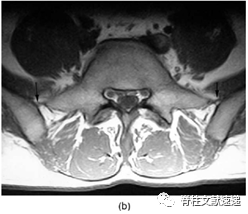

Hughes RJ等人的研究中提出,通过在MRI上识别髂腰韧带来确定椎体节段,因髂腰韧带起自L5横突。MRI上可以清除的看到髂腰韧带为L5横突延伸至髂后内侧嵴的单或双低信号带,如图6所示,当髂腰韧带出现在移行椎头侧椎体时,移行椎被认定为S1。如图7所示,当髂腰韧带出现在移行椎水平时,移行椎被认为L5。如图8所示,当没有找到在正常的髂腰韧带时,移行椎也被认定为L5,在这种情况下,我们假定横突的增宽增大导致较小的韧带发育。

图6注:T1加权像轴向MRI结果显示髂腰韧带(大箭头)被识别在移行椎(右上图片中小箭头)头侧椎体,该椎体被认为是L5,移行椎被认为是S1。